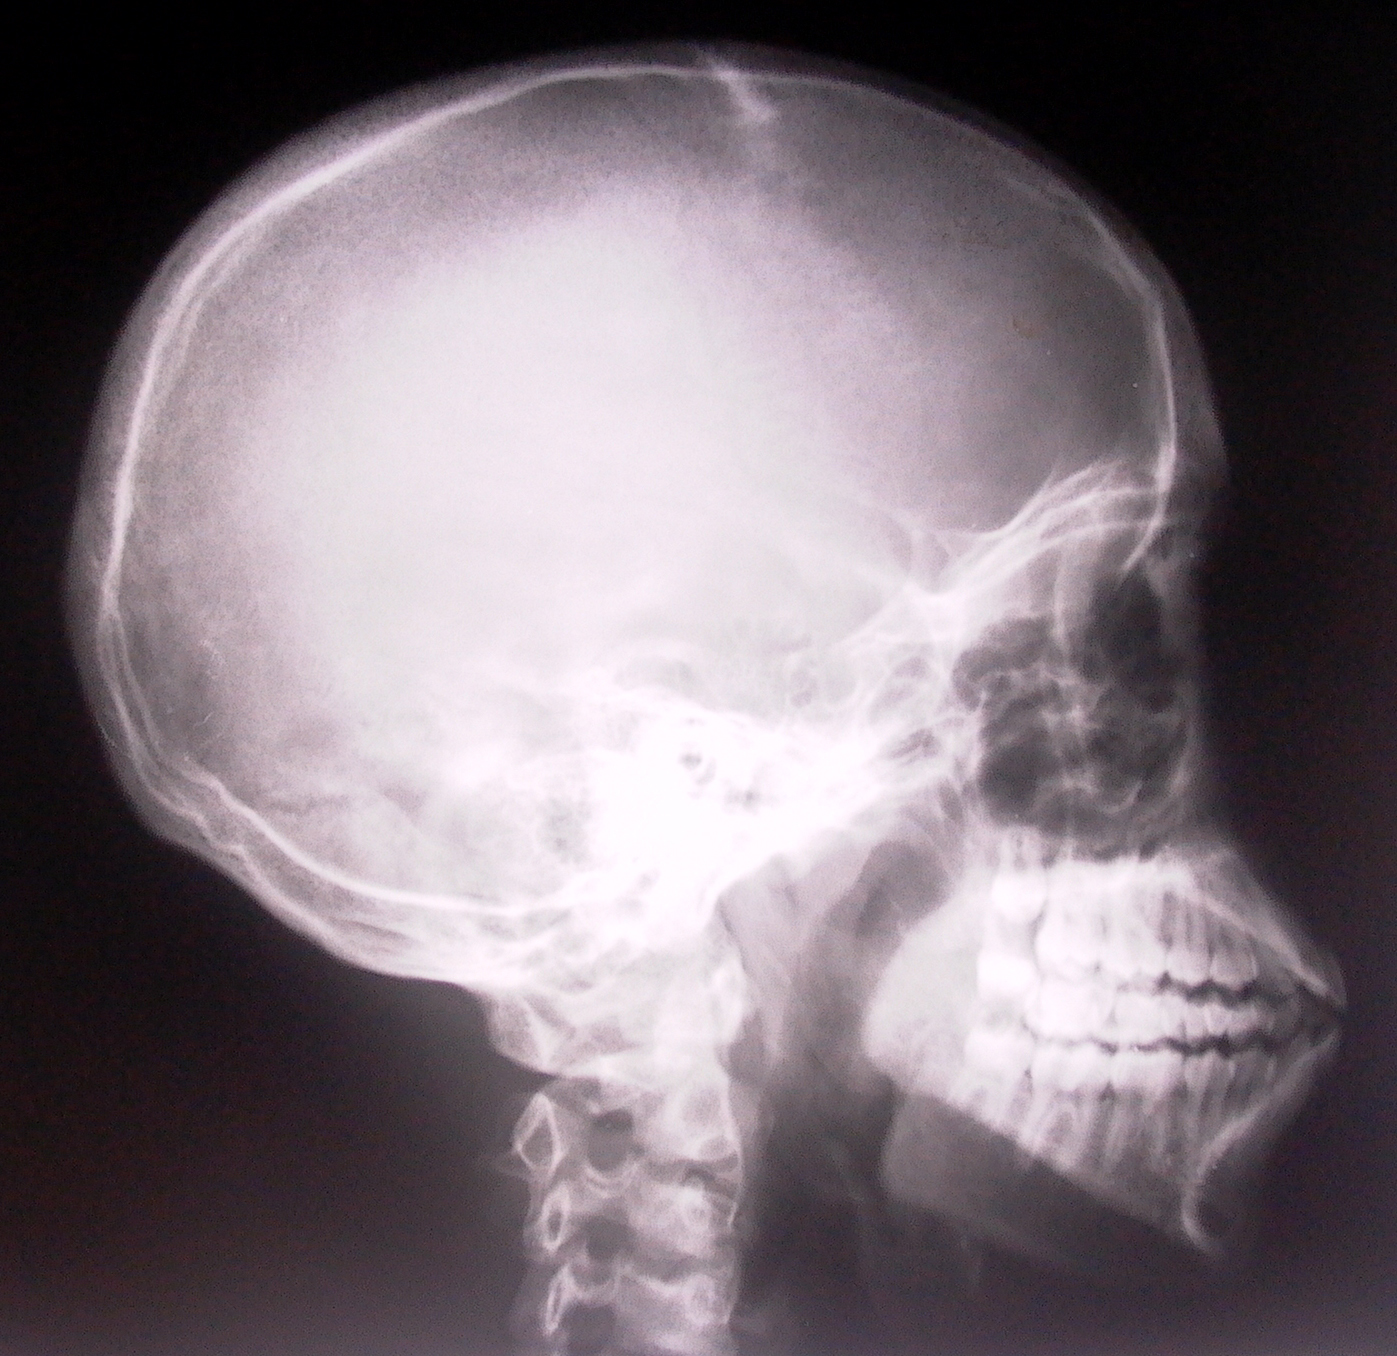

Анатомия мозга: Рентгеновские снимки для презентаций